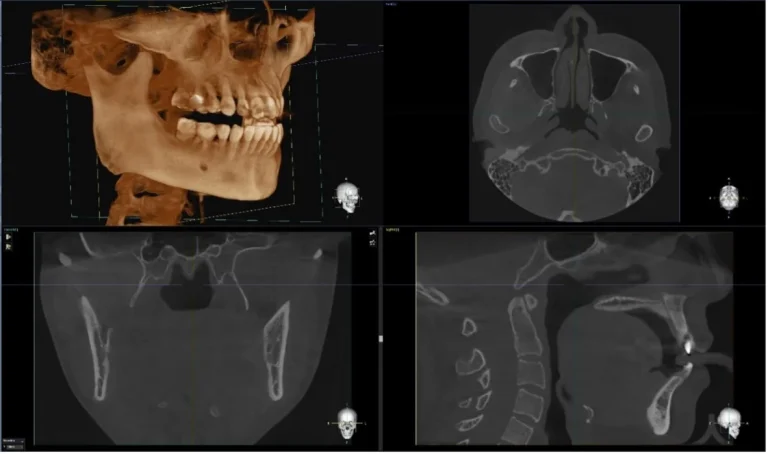

Dentium Rainbow™ CT 2-in-1 oferă imagini panoramice 2D și CBCT 3D într-un singur sistem, reducând costurile, spațiul ocupat și complexitatea infrastructurii radiologice. Sistemul este conceput pentru a răspunde nevoilor implantologilor, chirurgilor orali și medicilor proteticieni care au nevoie de o vizualizare clară a structurilor anatomice dento-alveolare și maxilo-faciale.

Precizie în diagnostic: voxel de 200 µm pentru CBCT și rezoluție panoramică de 120 µm/pixel.

Flux digital rapid: scanare în 19 secunde, reconstrucție automată și integrare DICOM.

Software intuitiv: vizualizare MPR/3D și compatibilitate CAD/CAM (3Shape, Exoplan, NobelGuide).